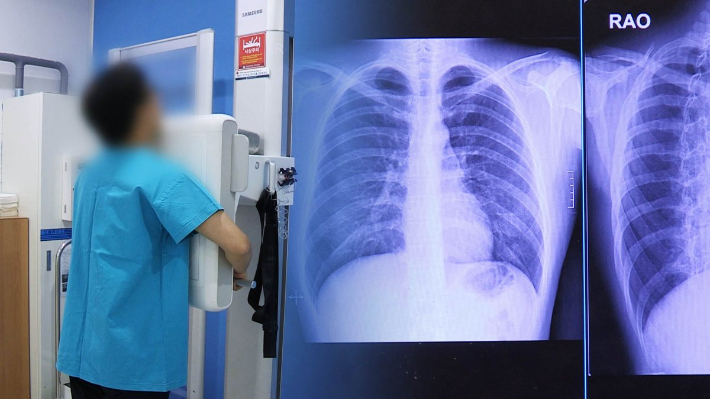

정부가 폐암 국가암검진 대상자를 확대하고, 대장암 검진에는 분변(대변) 잠혈검사 대신 대장내시경 검사를 도입하는 방안을 추진한다. 보건복지부는 24일 국가암관리위원회를 열어 이 같은 내용을 담은 '제5차 암 관리 종합계획(2026~2030)'을 의결했다.

폐암의 경우 해외 주요국 폐암 검진 현황 등을 토대로 오는 2028년부터 국가암검진 대상자를 확대할 예정이다. 폐암 국가암검진은 현재 30갑년(하루 한 갑씩 30년·2갑씩 15년) 이상의 흡연력이 있는 54~74세 폐암 고위험군에 시행되고 있는데, 대상자의 연령과 고위험군 기준 등을 완화하는 방안을 검토하기로 했다.

하지만 분변 잠혈검사에 대한 낮은 선호도로 인해 대장암의 경우 수검률이 2024년 기준으로 40.3%에 그쳐, 국가암검진사업 대상인 6대 암(위암·대장암·간암·폐암·유방암·자궁경부암) 중 가장 낮았다. 복지부는 폐암과 대장암 국가암검진 개선 등을 통해 6대 암의 조기 진단율을 지난해 57.7%에서 2030년 60.0%까지 올린다는 목표를 세웠다.